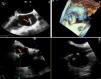

Incidental lead-associated masses are increasingly recognised in cardiac implantable electronic device (CIED) carriers undergoing transoesophageal echocardiography (TOE), often mimicking vegetations and raising concern for device-related infection. However, their true prevalence and clinical significance remain poorly characterised. This study aimed to assess the prevalence and clinical predictors of incidental non-infectious lead-associated masses.

ResultsA total of 120 patients were included, of whom 25 (20.8%) had incidental non-infectious lead-associated masses. No significant differences were observed between groups regarding age, sex, cardiovascular risk factors, CIED type or echocardiographic parameters. Therapeutic anticoagulation was significantly less frequent in patients with lead masses (20.0% vs 41.1%; P=.027). In multivariate analysis, therapeutic anticoagulation was independently associated with a lower likelihood of lead masses (adjusted OR, 0.25; 95% CI, 0.06–1.00; P=.050).

ConclusionsIncidental non-infectious lead-associated masses are a relatively frequent finding in patients with CIED undergoing TOE. The absence of anticoagulation was the only independent predictor identified, suggesting a possible thrombotic mechanism. These findings support a conservative diagnostic approach in asymptomatic patients, to avoid unnecessary interventions.